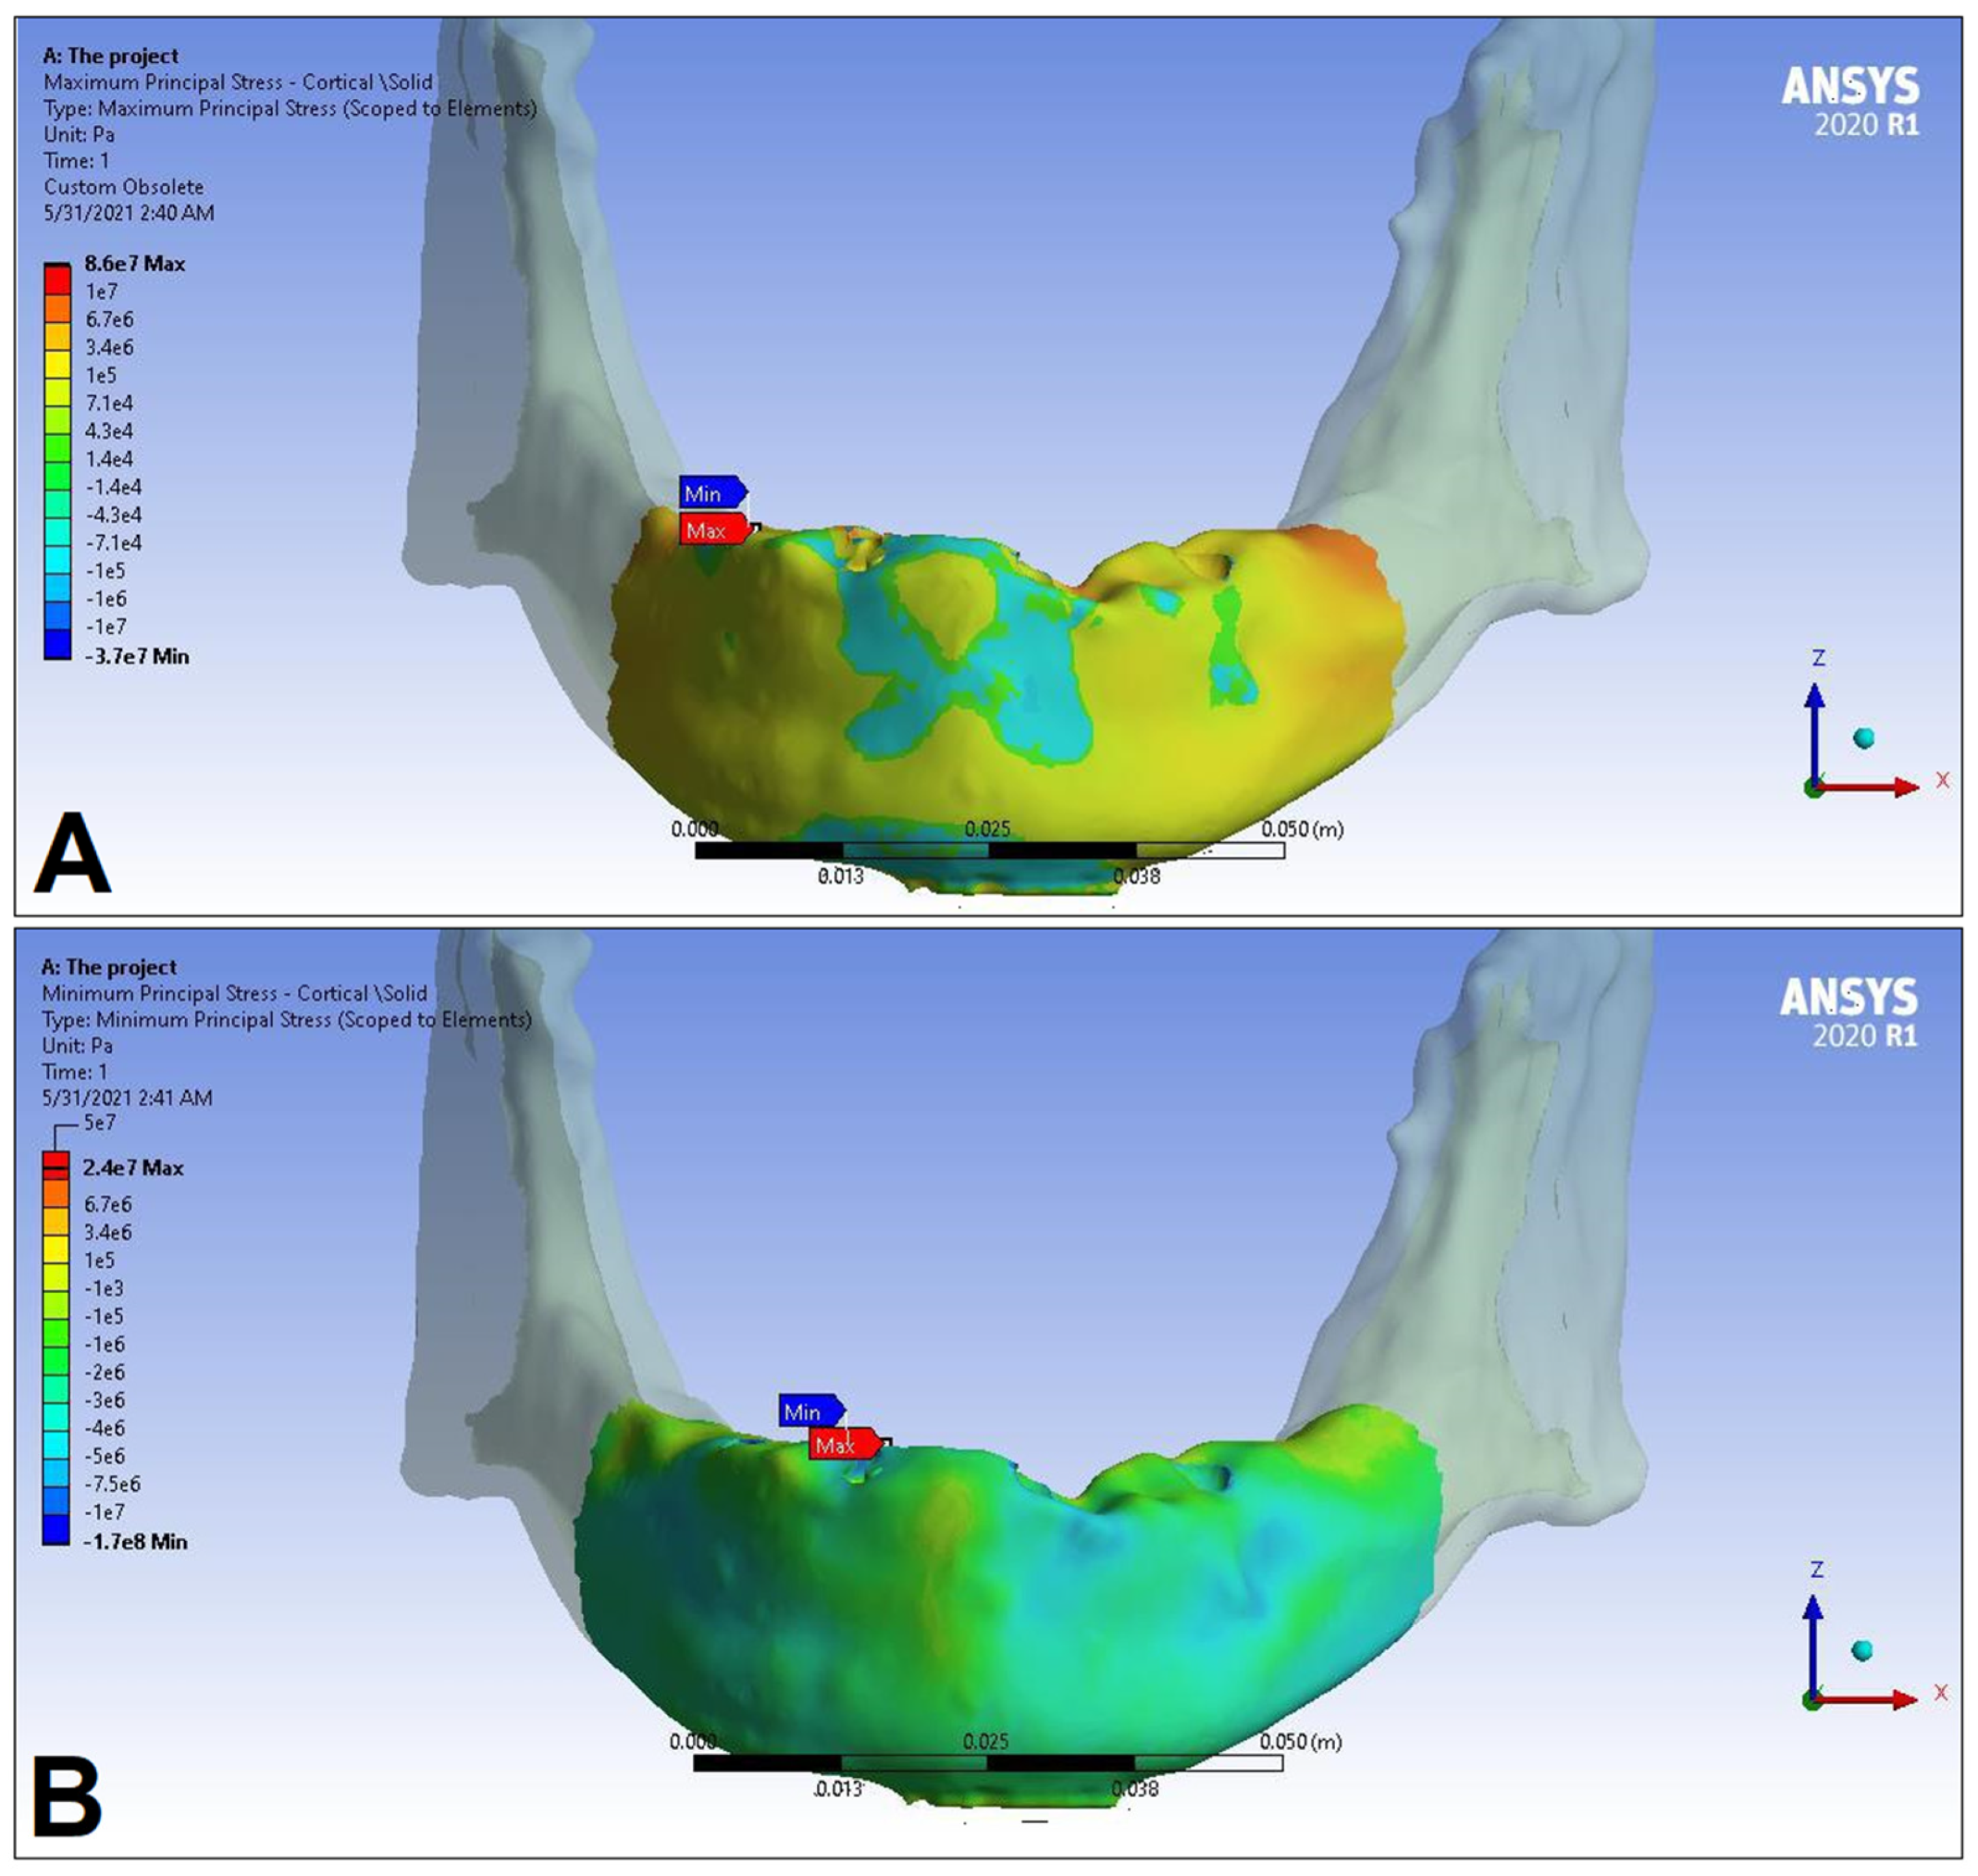

3. Results

| LC1 | LC2 | LC3 | LC4 | ||||||

|---|---|---|---|---|---|---|---|---|---|

| S1 | S2 | S1 | S2 | S1 | S2 | S1 | S2 | ||

| Cortical bone | Pmax [MPa] | 76.39 | 88.51 | 89.57 | 102.98 | 85.63 | 95.48 | 81.02 | 93.15 |

| Pmin [MPa] | −115.30 | −222.76 | −136.4 | −265.35 | −172.30 | −252.61 | −125.20 | −235.32 | |

| Trabecular bone | Pmax [MPa] | 2.49 | 2.24 | 3.03 | 2.62 | 2.95 | 2.52 | 2.92 | 2.59 |

| Pmin [MPa] | −2.81 | −2.89 | −3.34 | −3.38 | −3.25 | −3.25 | −3.49 | −3.52 | |

| Peqv [MPa] | 166.40 | 244.92 | 166.36 | 279.69 | 164.36 | 265.58 | 142.27 | 260.77 | |